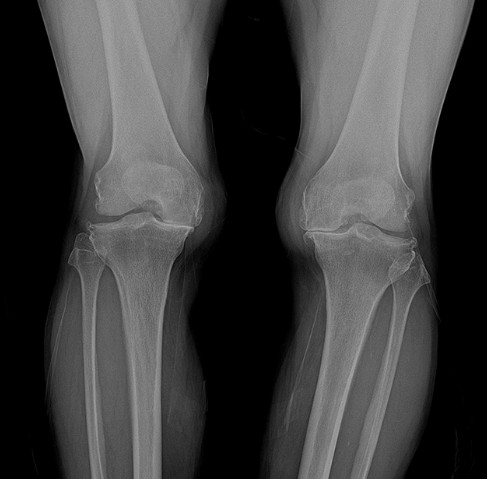

퇴행성관절염이란 관절을 보호하고 있는 연골의 점진적인 손상이나 퇴행성변화로 인해 관절을 이루고 있는 뼈와 인대 등에 손상이 일어나 통증과 염증이 생기는 질환입니다. 퇴행성 관절염은 주로 60~65세 이상 노인의 80%가 겪고 있는 아주 흔한 무릎 질환으로 최근에는 생활습관, 비만 등 여러가지 원인으로 젊은 층에서도 많이 발생하고 있습니다. 퇴행성 관절염에 걸리면 연골이 분해되면서 생기는 염증물질이 통증을 일으키게 되고 연골 파괴를 더 부추겨 관절 분해가 더 가속화되는 악순환이 발생합니다. 또한 연골이 분해되면서 관절 간격이 좁아지고 다리가 휘게 되는 내반 변형이 발생하면서 겉에서 보기에도 다리가 휘어 보이는 오다리가 생기는 부작용이 발생합니다.